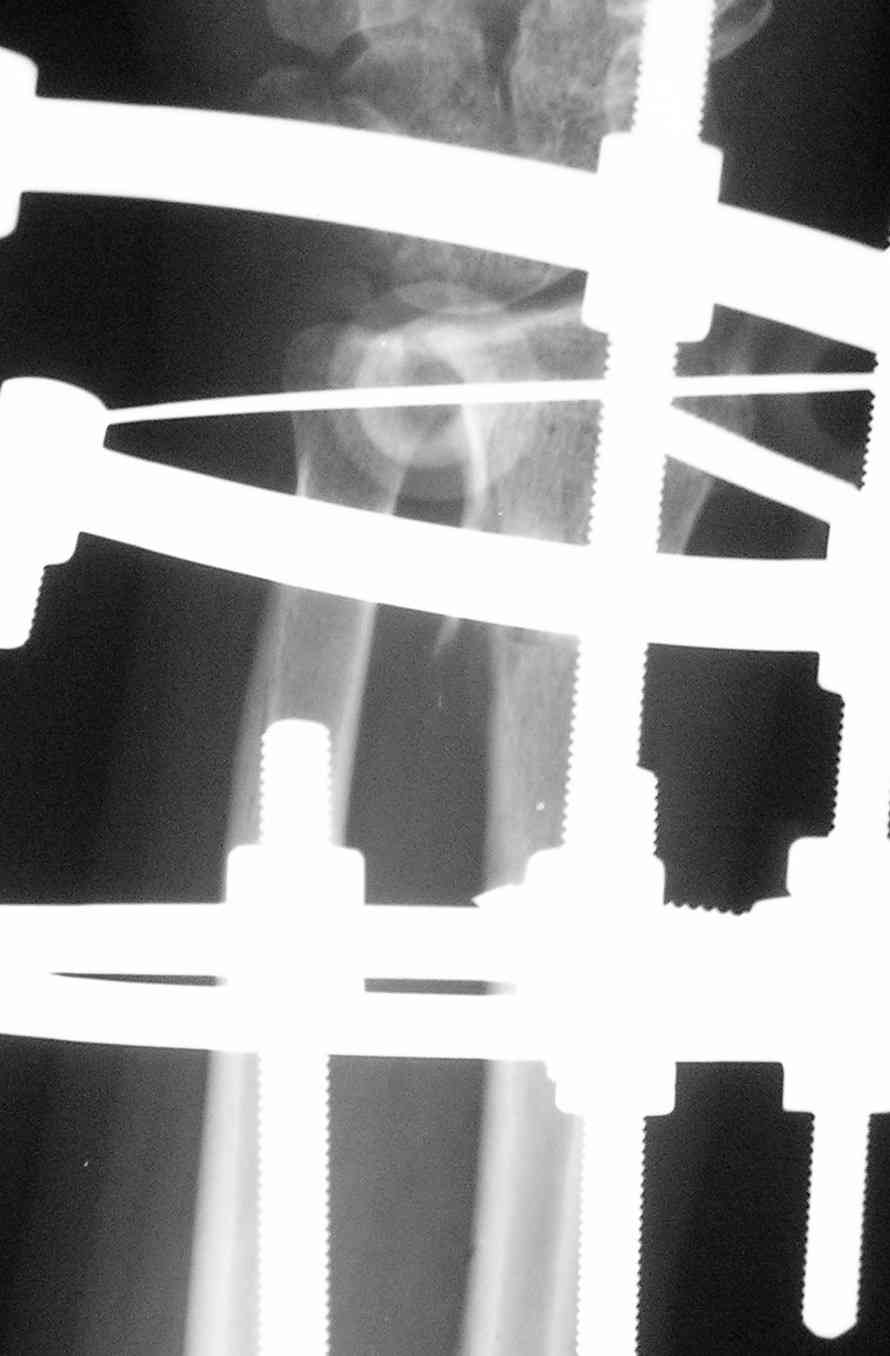

Спице-стержневой аппарат с компактотомией лучевой кости, костная пластика локтевой с удалением пластины. Не комфортно, но больше шансов на благоприятный исход. Заканчиваю лечение с похожей деформацией лучевой кости.

У больного/ой кроме перелома лучевой кости и шиловидного отростка локтевой, разрыв дистального радиоульнарного сочленения, перелом ладьевидной кости и ладьевидно-полулунная диссоциация.

Если позволите свое мнение, не стал бы лечить аппаратом эту травму, перелом луча не консолидировался: открытая репозиция+ костная пластика+ пластина, синтез ладьевидной кости, по возможности шов ладьевидно полулунной связки,

если восстановить связку не представляется возможным, фиксация 2 спицами.